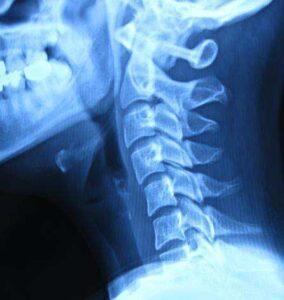

어깨만의 문제라면 목의 위치에 상관없이 모두 다 잘 올라가지 않아야 하지만, 목의 위치에 따라 어깨를 들어 올릴 때의 통증이나 들어 올리는 정도가 변하면 척추에 기인한 어깨 통증으로 판단할 수 있고 추나요법이 필요합니다.